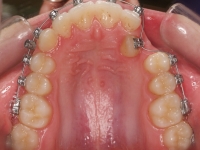

Clase II paciente 15 años

La paciente O.O. acude a nuestra consulta por:

– Canino 13 e incisivo lateral 42 en posición ectópica.

– Canino 23 incluido.

Con lo que decide realizarse un tratamiento de ortodoncia de duración de 24 meses con brackets damon Q.